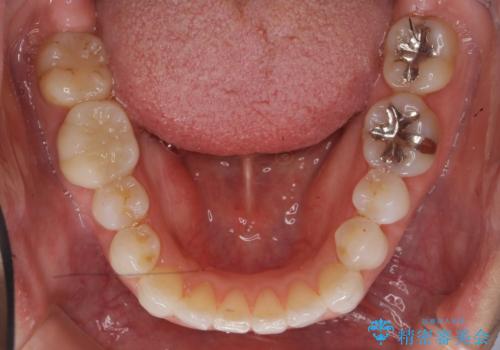

30代女性 前歯のがたつき

- 前歯のがたつきを主訴に来院。

右下の奥の銀歯も治療しています。

下の前歯を下げるため、IPR(歯をわずかに削る処置)を行っています。